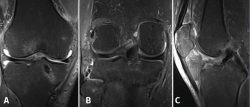

The computed tomography (CT) study evidenced a fracture of the posterior region of the internal tibial plateau with millimetric collapse and sub-centimetre avulsed fragments located immediately medial to the posterior cruciate ligament (PCL), together with a small fracture in the posterior cortical layer of the external tibial plateau without collapse, displacement or comminution (Figure 2).

Figure 2. The axial (A), sagittal (B) and coronal (C) computed tomography views show the avulsed bone fragments dependent upon the posterior root of the medial meniscus, near the insertion of the posterior cruciate ligament.

Magnetic resonance imaging (MRI) revealed multiple contusion edema zones with severe partial rupture of the ACL and grade I-II lesion of the PCL, with normal insertion at distal level (Figure 3A). In addition, proximal distension of the medial collateral ligament (MCL) and lateral collateral ligament (LCL) was observed, together with damage to the external meniscus posterior root (LaPrade type 4) (Figure 3B) associated to fracture of the external tibial plateau and deinsertion of the internal meniscus posterior root (LaPrade type 5) (Figure 3B) with meniscal extrusion (Figure 3C).

Figure 3. Magnetic resonance imaging study showing post-contusion edema of the tibia, with rupture of the anterior cruciate ligament. The posterior cruciate ligament appears correctly inserted in the sagittal view (A); the coronal view shows a radial lesion of the external meniscal root and bone avulsion with a bone fragment of the external root (B), causing extrusion of the internal meniscus (C).